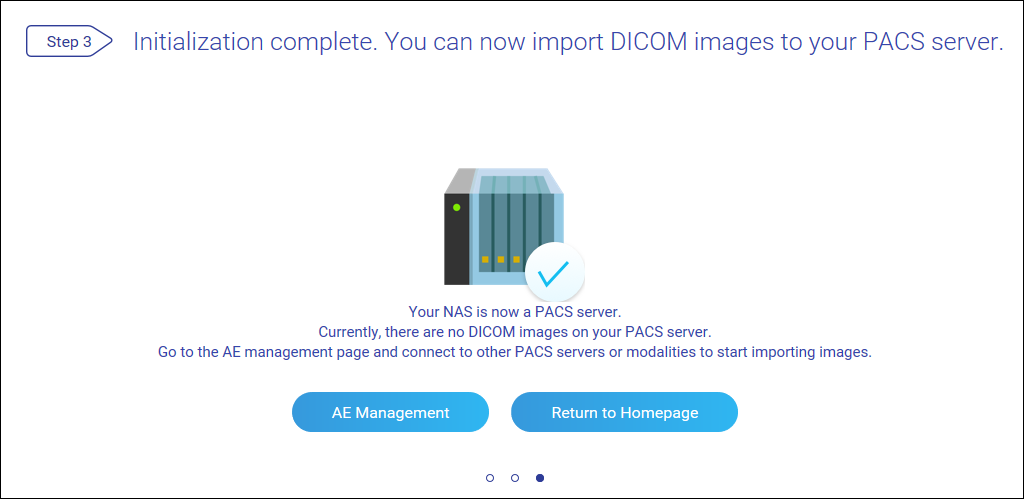

将 NAS 设置为 PACS 服务器

首次登录后,MediQPACS 管理员必须将 NAS 初始化为 PACS 服务器。